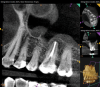

The diagnosis for tooth No. 14 was pulpal necrosis with asymptomatic apical periodontitis. NSRCT was completed (Figure 9), followed by full-coverage restorative care performed by the general dentist. A 3-month follow-up revealed resolution of prior sinus symptoms, normal clinical findings, and healing radiographic pathology, including periapical pathology and associated maxillary sinus mucositis (Figure 10 and Figure 11).

Both of these cases illustrate the improvement in sinus pathology findings from preoperative CBCT scans to postoperative recall CBCT scans following NSRCT (Figure 4, Figure 10, and Figure 11). In addition, in both instances the re-establishment of the previously obliterated cortical boundary between the apex and maxillary sinus was impressive. Clinically, the resolution of sinusitis symptoms in both patients after receiving nonsurgical endodontic therapy was quite notable. Despite the absence of specific dental pain, these patients' sinusitis symptoms could not have been alleviated without the endodontic interventions due to the odontogenic etiology of their disease. These two cases demonstrate the pivotal role of CBCT imaging in diagnosis and recall as well as the success of NSRCT when treating cases of MSEO.

Fig 10. CBCT imaging at 3-month follow-up showing signs of healing and decrease in maxillary sinus mucositis. Fig 10: Sagittal view, buccal roots No. 14. Fig 11: Sagittal view, palatal root No. 14.

Figure 10

Fig 11. CBCT imaging at 3-month follow-up showing signs of healing and decrease in maxillary sinus mucositis. Fig 10: Sagittal view, buccal roots No. 14. Fig 11: Sagittal view, palatal root No. 14.

Figure 11